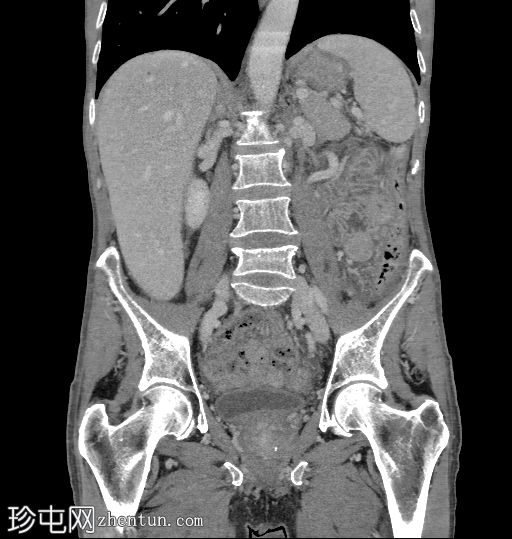

冠状位

冠状位增强扫描

门静脉期

盲肠内壁可见多条明显的血管通道,并可见局灶性强化。

动脉期可见一条早期充盈的静脉。静脉期可更清晰地显示扩张的引流静脉。未见活动性出血。

结肠镜检查证实存在小型盲肠动静脉畸形(AVM)。

多期CT扫描中血管发育不良的典型表现是血管簇或血管缠结。